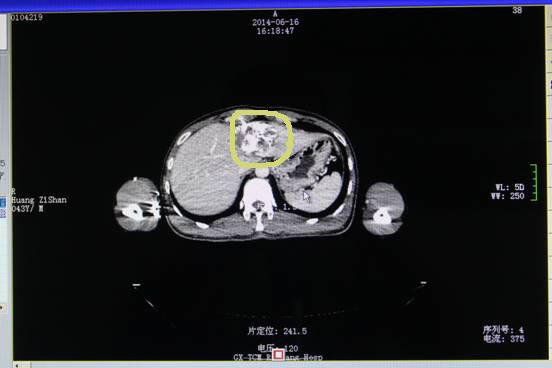

2014年6月16日,黄先生按照医生的嘱咐进行复查并准备进行下一环节——射波刀治疗。

射波刀后肿瘤明显缩小